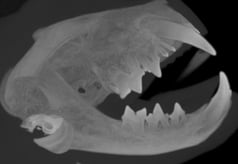

A cat presented with a temporomandibular joint (TMJ) luxation after a fall from a shelf. Initial attempts to reposition the TMJ at an emergency clinic were followed by a referral to ensure no fractures. The treatment involved the 'button' technique for TMJ stabilization, which was successful after three weeks of esophageal tube feeding. Post-treatment, the cat returned to normal function, although slight TMJ mobility and subluxation were noted. Imaging confirmed no fractures, and Ethilon with 3 buttons was used for stabilization, to be removed in 7-14 days. Follow-up imaging, specifically Cone Beam Computed Tomography (CBCT), was recommended one year later to monitor dental development.